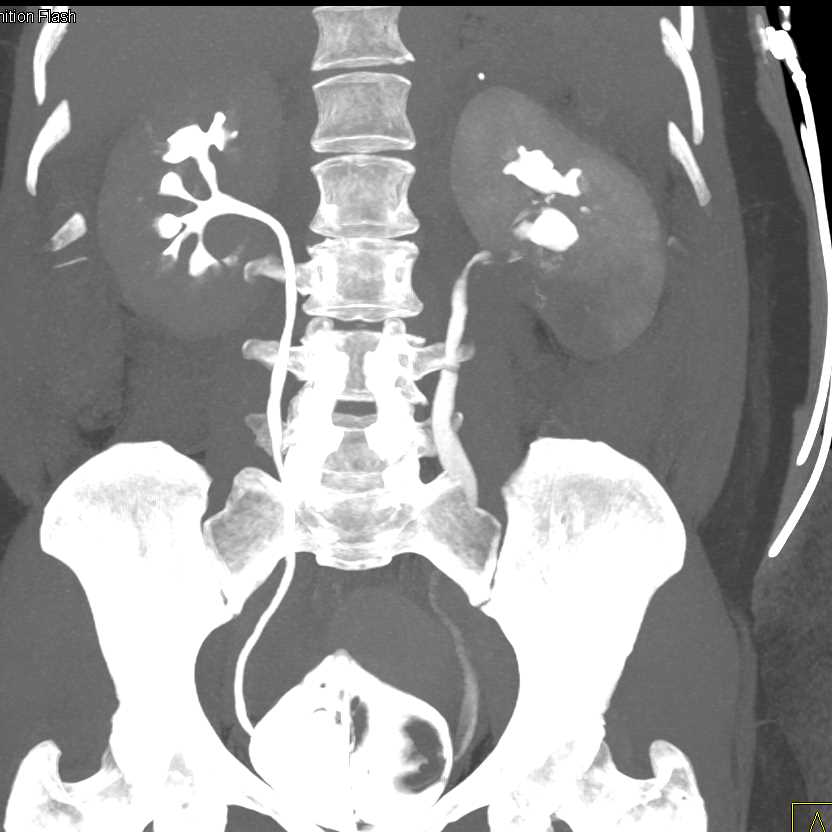

Acute Pyelonephritis Right Kidney